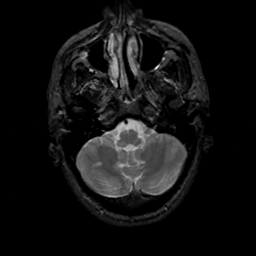

MR Study #22, December 1, 1991 -- Slice #9

[Home][Help][Clinical][Tour 1][Tour 2] Slice 9